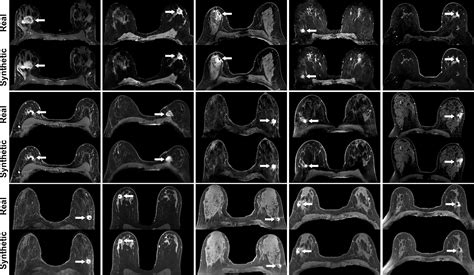

The primary purpose of adding a contrast agent during your scan is to improve the visibility of internal structures. Without contrast, some tissues may appear similar in density, making it difficult for a physician to identify subtle abnormalities. By using a contrast agent, the substance travels through your blood vessels and accumulates in areas of increased blood flow, such as tumors, areas of inflammation, or damaged blood vessels. This “enhancement” makes these areas appear brighter or more defined on the resulting images.

• Detecting tumors: Contrast helps distinguish between benign and malignant growths by showing how much blood supply they receive.

After the scan is complete, the images are sent to a radiologist. They analyze the scan to compare the non-contrast and contrast-enhanced images. The “enhancement” patterns allow the radiologist to write a detailed report for your primary physician. This report usually outlines findings in clinical terms, noting the presence or absence of abnormalities. It is important to remember that the MRI report is just one part of your diagnostic puzzle; your doctor will correlate these results with your physical exam and other lab findings to finalize a diagnosis and treatment plan.